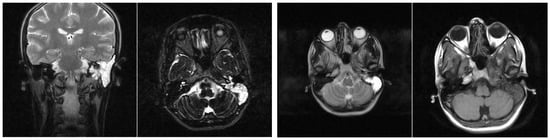

3.1.2. Computed Tomography and Magnetic Resonance Imaging

| MRI Aspects | Number of Patients | Percentage |

|---|---|---|

| Edema | 128 | 100% |

| Cholesteatoma | 40 | 31.25% |

| Exocranial extensions | 40 | 31.25% |

| Intracranial extensions | 32 | 25% |

| Inner ear damage | 20 | 15.62% |